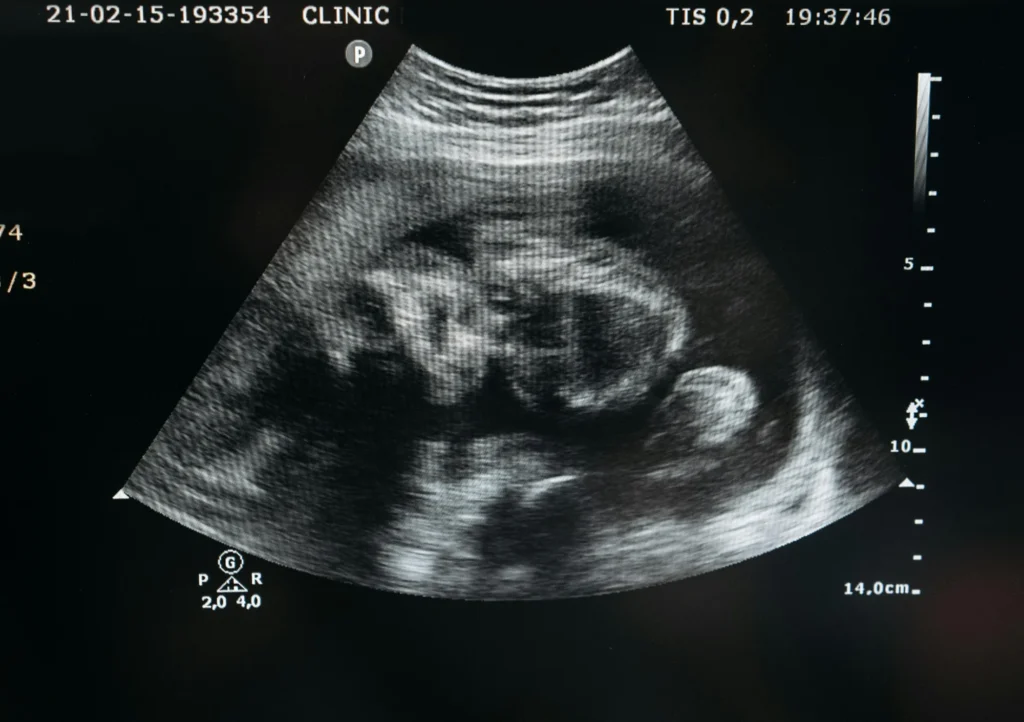

¿Cómo te Acompañamos en tu Proceso de Embarazo en Clínica Vie?

En Clinique Vie acompañamos cada etapa de la salud reproductiva con estudios genéticos y diagnósticos avanzados orientados a la prevención, el seguimiento del embarazo y la planificación familiar. Nuestro laboratorio ofrece pruebas de alta precisión que permiten obtener información clave para cuidar la salud materna, fetal y reproductiva de forma personalizada, segura y responsable.

Gracias a la medicina genética, hoy es posible anticiparse a posibles riesgos, mejorar el control del embarazo y tomar decisiones informadas desde el inicio.